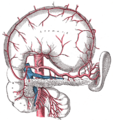

الشريان | Splenic artery |

الوريد | Splenic vein |

Nerve | Splenic plexus |